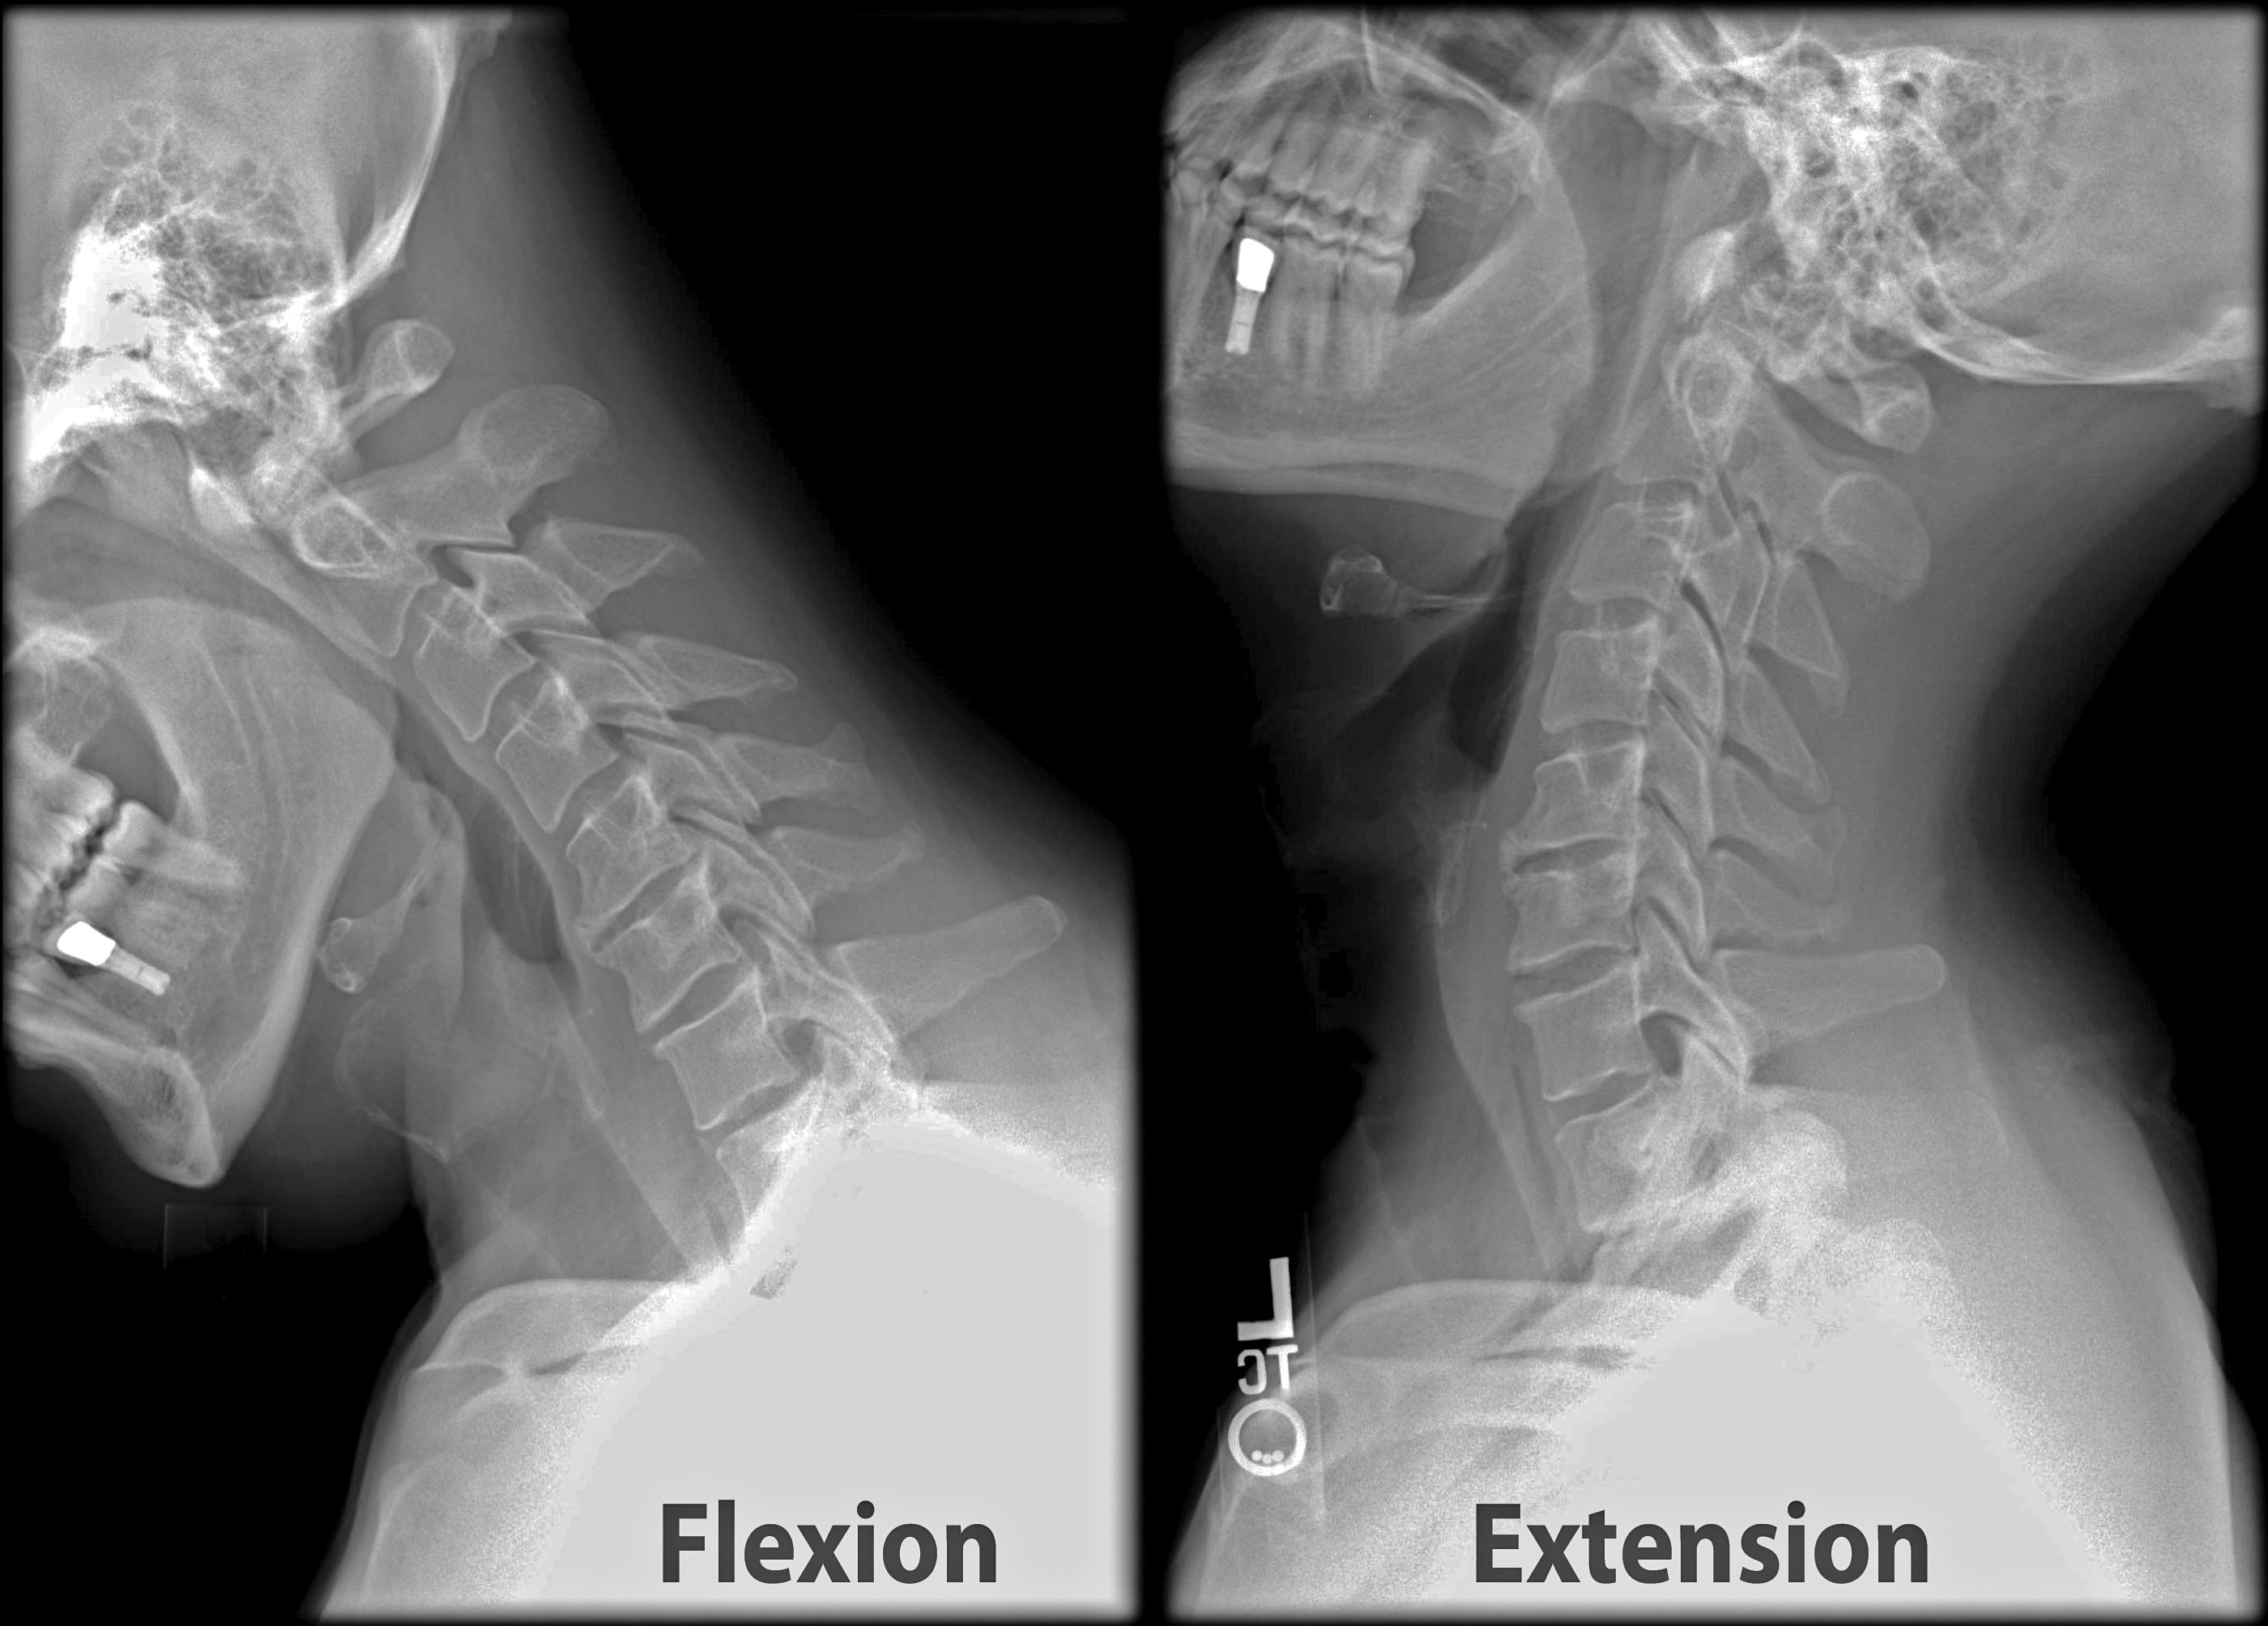

Психосоматика и подвывих шейного позвонка: Визуализация и объяснения